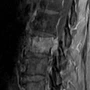

CT and MRI provide complementary information for the spinal instability tumor score. CT is particularly useful for cortical destruction, lytic versus blastic lesions spine characterization, fracture morphology, posterior element involvement tumor assessment, and subtle collapse. MRI is essential for marrow replacement, epidural tumor extension, neural element compression, paraspinal soft tissue disease, and radiation oncology spine lesions planning.

Bone lesion quality is commonly assessed by CT when available. Lytic disease receives a higher score because it usually reduces osseous structural integrity more than blastic disease. Mixed lesions receive an intermediate score. MRI may show marrow replacement before cortical destruction is obvious, but distinguishing lytic from blastic disease can be more challenging on MRI alone.

Spinal alignment tumor involvement should be assessed for translation, subluxation, kyphosis, scoliosis, or new deformity attributable to tumor. Translation or subluxation carries the highest score within this component because it suggests more advanced mechanical disruption. Vertebral body collapse is evaluated by estimating height loss and the extent of vertebral body involvement. A lesion involving more than half of the vertebral body may receive a score even before measurable collapse occurs.